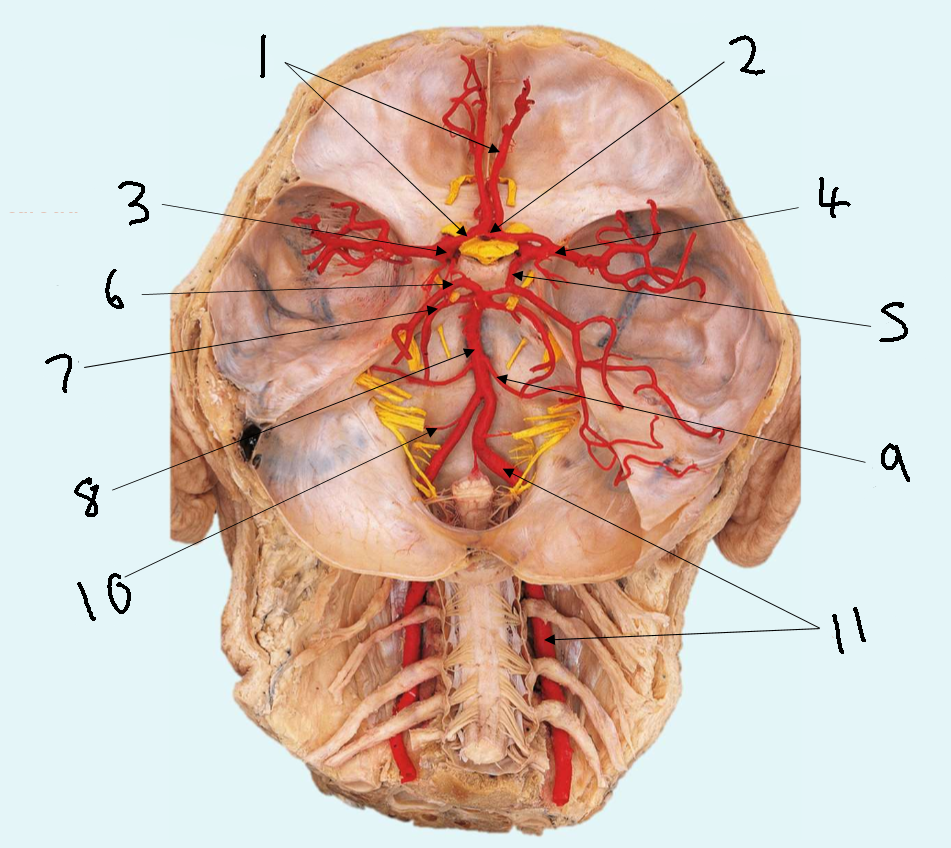

What is 1?

anterior communicating artery

What is 2?

anterior cerebral artery

What is 3?

middle cerebral artery

What is 4?

internal carotid artery

What is 5?

posterior communicating artery

What is 6?

posterior cerebral artery

What is 7?

superior cerebellar artery

What is 8?

pontine arteries

What is 9?

basilar artery

What is 10?

anterior inferior cerebellar artery

What is 11?

vertebral artery

What is 12?

posterior inferior cerebellar artery